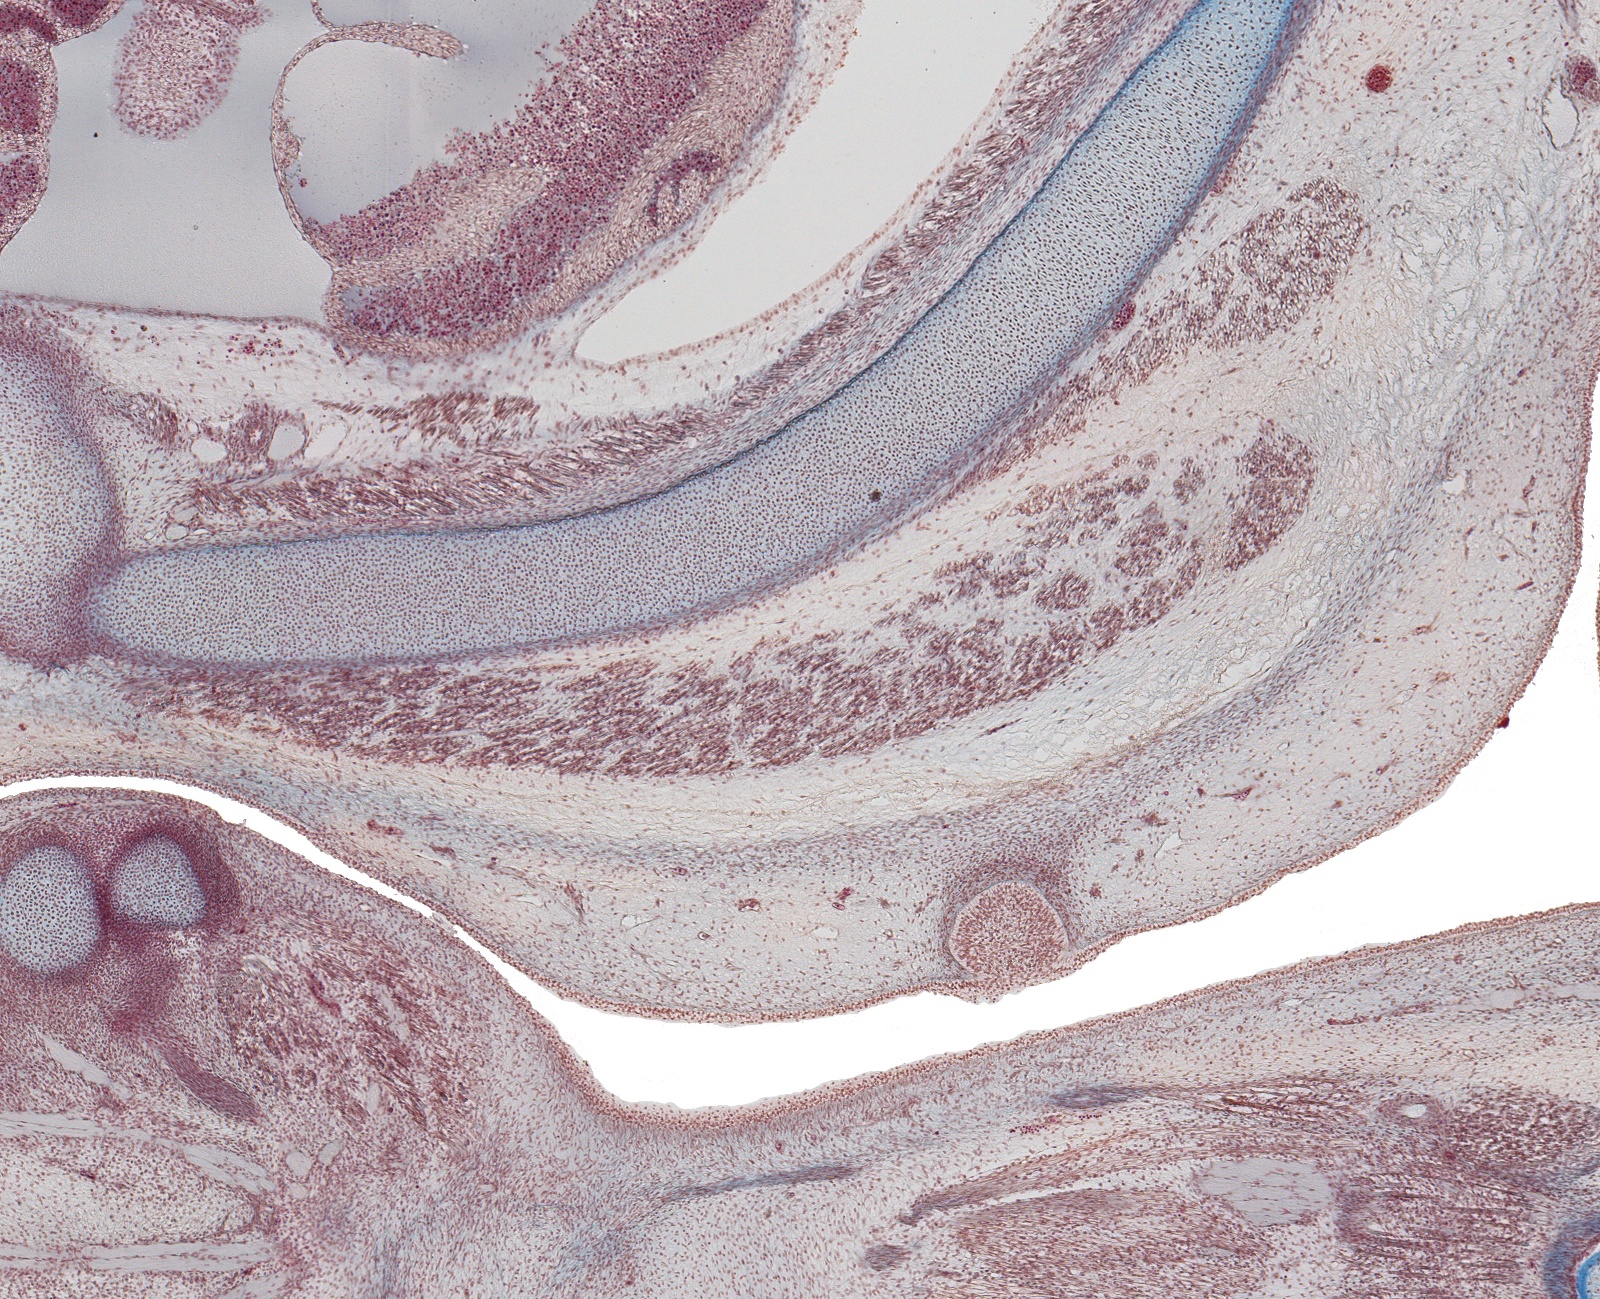

Tissue

–

Lt. Nipple and Costal Cartilage

Carnegie Embryo #9226

Location:

105-01-01